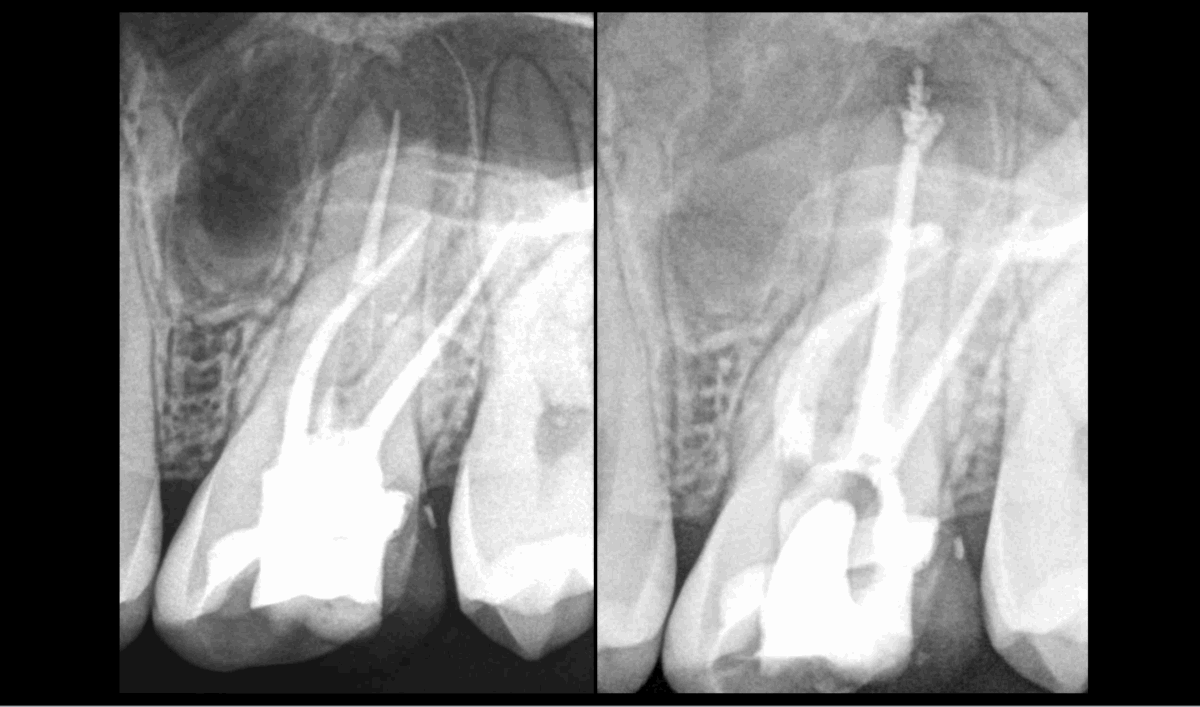

🆕 Essai au cabinet d’un nouvel instrument revenu sur le marché il y a peu : 𝐥𝐞 𝐒𝐀𝐅 (𝐒𝐞𝐥𝐟–𝐀𝐝𝐣𝐮𝐬𝐭 𝐒𝐲𝐬𝐭𝐞𝐦).

🔹 𝐂𝐚𝐫𝐚𝐜𝐭𝐞̀𝐫𝐞 𝐞𝐱𝐩𝐚𝐧𝐬𝐢𝐟 𝐝𝐞 𝐩𝐚𝐫𝐭 𝐬𝐚 𝐟𝐨𝐫𝐦𝐞 𝐞𝐭 𝐬𝐨𝐧 𝐚𝐥𝐥𝐢𝐚𝐠𝐞, 𝐬’𝐚𝐝𝐚𝐩𝐭𝐚𝐧𝐭 𝐦𝐢𝐞𝐮𝐱 𝐪𝐮𝐞 𝐛𝐢𝐞𝐧 𝐝𝐞𝐬 𝐢𝐧𝐬𝐭𝐫𝐮𝐦𝐞𝐧𝐭𝐬 𝐚̀ 𝐥’𝐚𝐧𝐚𝐭𝐨𝐦𝐢𝐞 𝐜𝐚𝐧𝐚𝐥𝐚𝐢𝐫𝐞.